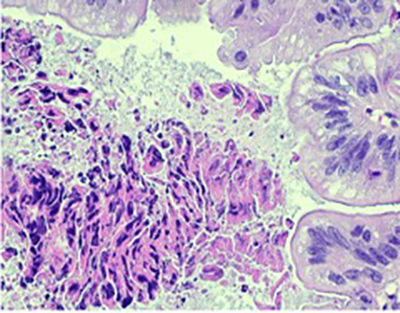

Histopathologic examination showed fragmented specimen containing adenocarcinoma, characterized by relatively well formed glands with cribriform glands in some areas. The epithelial cells were relatively uniform with basally oriented nuclei and intracytoplasmic mucin was present in a subset of cells. Some areas contained areas of necrotic cellular debris within the lumens of the neoplastic glands. No areas of non-atypical endometrial hyperplasia or endometrial intraepithelial neoplasia were identified. There were fragments of leiomyomas in the background. Immunohistochemical analysis demonstrated the adenocarcinoma cells to be positive for CK20, CDX-2, SATB-2 (patchy), MUC2 (patchy) and CEA. They were negative for CK7, PAX-8, GATA-3, ER, PR, Vimentin and hrHPV in-situ. The p16 and MUC6 showed rare positive neoplastic cells, and p53 demonstrated a wild type pattern. Mismatch repair proteins were intact. The combined morphologic and immunohistochemical features support and adenocarcinoma with an enteric/gastrointestinal phenotype. The case was finalized as moderately differentiated adenocarcinoma with intestinal/enteric phenotype. In the absence of any notable conventional endometrioid adenocarcinoma or precursor endometrial proliferation, the differential diagnosis included a metastasis (likely from colorectal origin or other sites which may acquire an intestinal phenotype, and an unusual primary endometrial carcinoma with pure intestinal metaplasia/differentiation. Additional workup to exclude extrauterine primary sites was recommended.

Fig. 1 Adenocarcinoma embedded in endometrial stroma (A and B). Adenocarcinoma with dirty necrosis (C) and intracytoplasmic mucin (D). The malignant cells are negative for CK-7 (E) and positive for CK-20 (F), CDX-2 (G), SATB-2 (H).